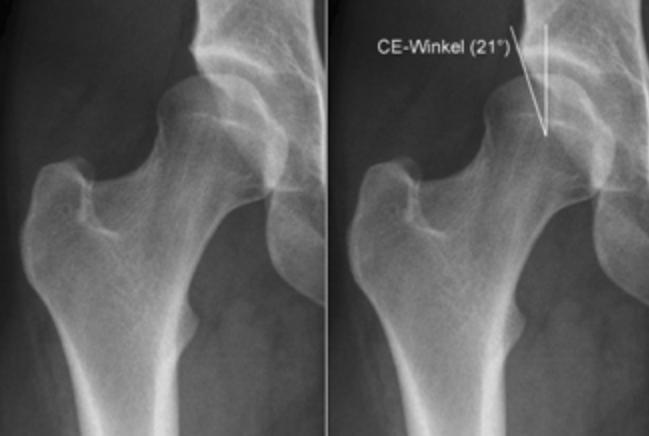

Дисплазия тазобедренного сустава относится к неправильному росту во внутренней полости тазобедренного сустава. Это также может привести к плохой осанке, которая известна как вывих бедра или вывих бедренного сустава. Головка бедра частично или полностью удалена относительно внутренней полости тазобедренного сустава, что означает, что головка не присутствует должным образом во внутренней полости, как показано на следующих изображениях.

Это может привести к повышению давления на область полости, что может вызвать преждевременный износ суставного хряща, что иногда требует замены сустава в раннем возрасте.Лечение: на ранней стадии с незначительным повреждением суставного хряща, есть возможность исправить это отклонение с помощью трехмерных пятен таза, как показано на следующих изображениях.